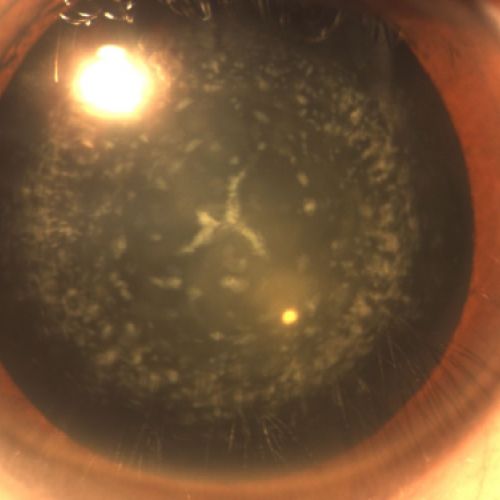

Imágenes de cataratas desde nuestra clínica

Así se ven las cataratas, conoce el caso de algunos de nuestros pacientes

Ejemplo de catarata en un ojo

Cataratas